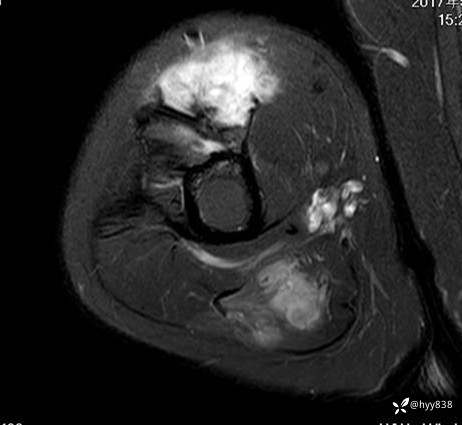

SAG T1WI+PDWI fs

COR T2WI

CE